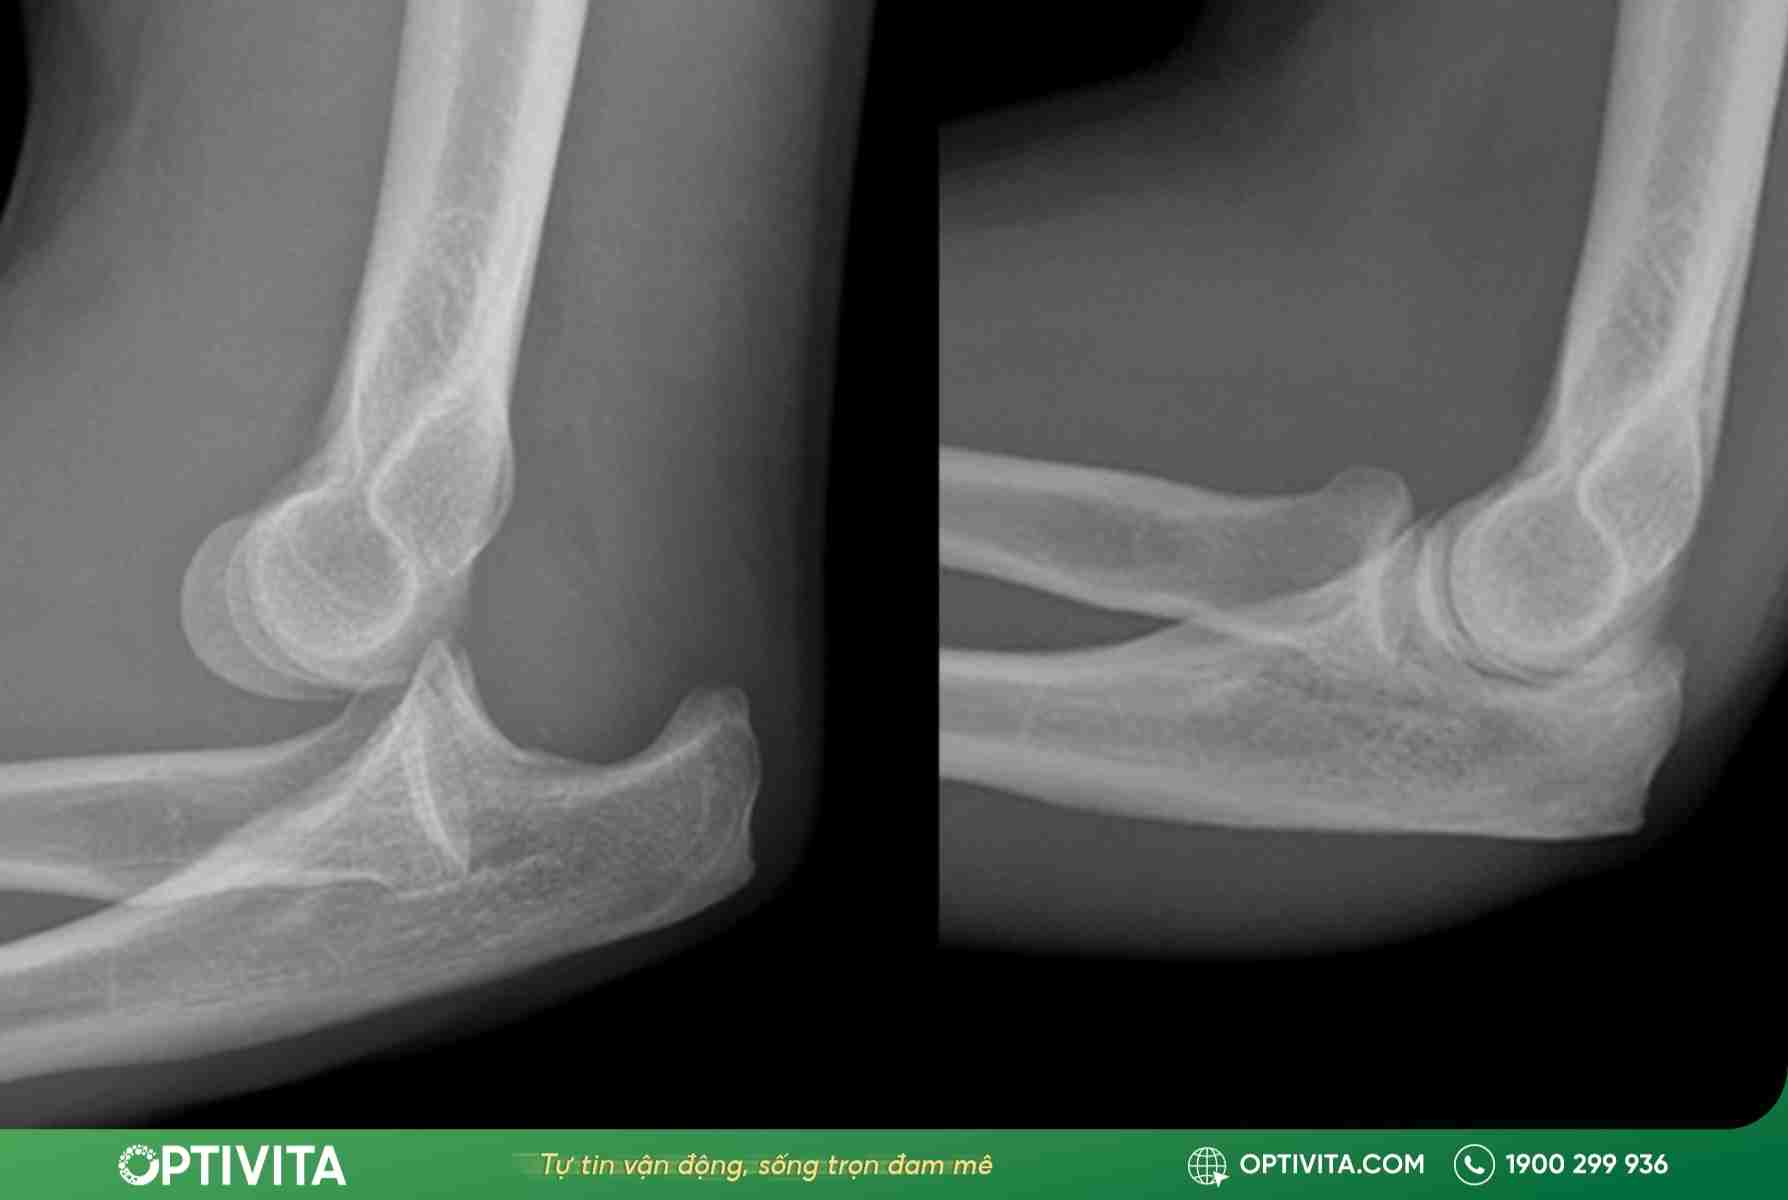

Sau khi thăm khám và chụp X-quang để xác định mức độ tổn thương của cấu tạo khớp khuỷu tay, bác sĩ sẽ quyết định phác đồ điều trị phù hợp nhất là bảo tồn hay can thiệp ngoại khoa:

Phương pháp nắn chỉnh kín (Closed Reduction)

Đây là phương pháp ưu tiên cho các ca trật khớp mới và đơn thuần (không kèm gãy xương phức tạp).

- Quy trình: Bệnh nhân sẽ được dùng thuốc giảm đau, giãn cơ hoặc gây tê. Bác sĩ chấn thương chỉnh hình sẽ thực hiện các thao tác nắn chỉnh khớp khuỷu tay chuyên môn để đưa đầu xương trượt nhẹ nhàng về lại ổ khớp.

- Cố định sau nắn: Ngay sau khi khớp vào vị trí, cánh tay sẽ được bó bột hoặc nẹp bột từ cánh tay xuống bàn tay ở tư thế khuỷu gấp 90 độ. Thời gian cố định thường kéo dài từ 2 – 3 tuần để tạo điều kiện cho dây chằng và bao khớp lành lại.